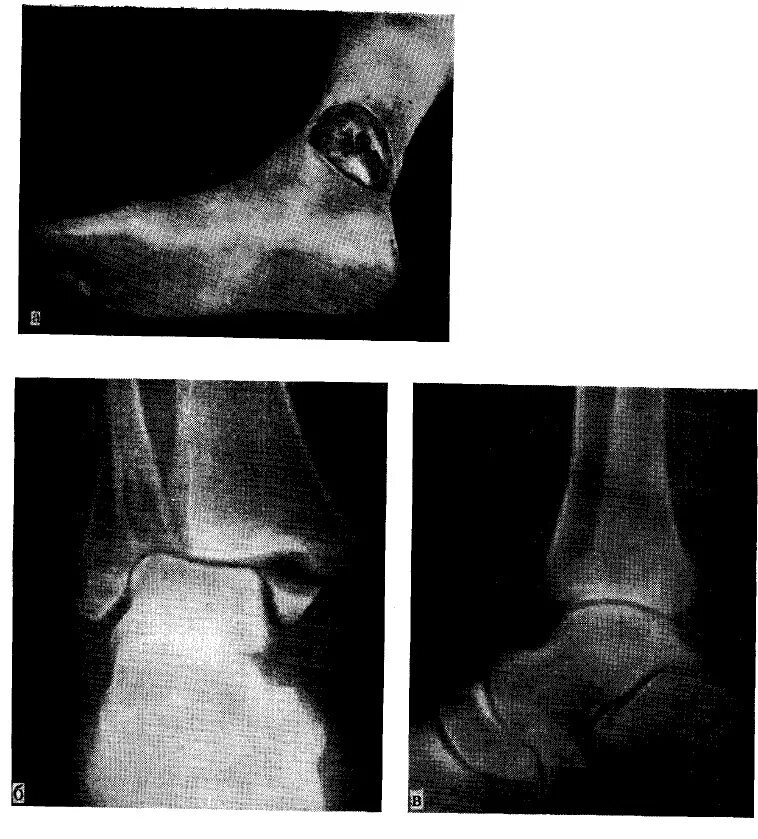

Вывих со смещением